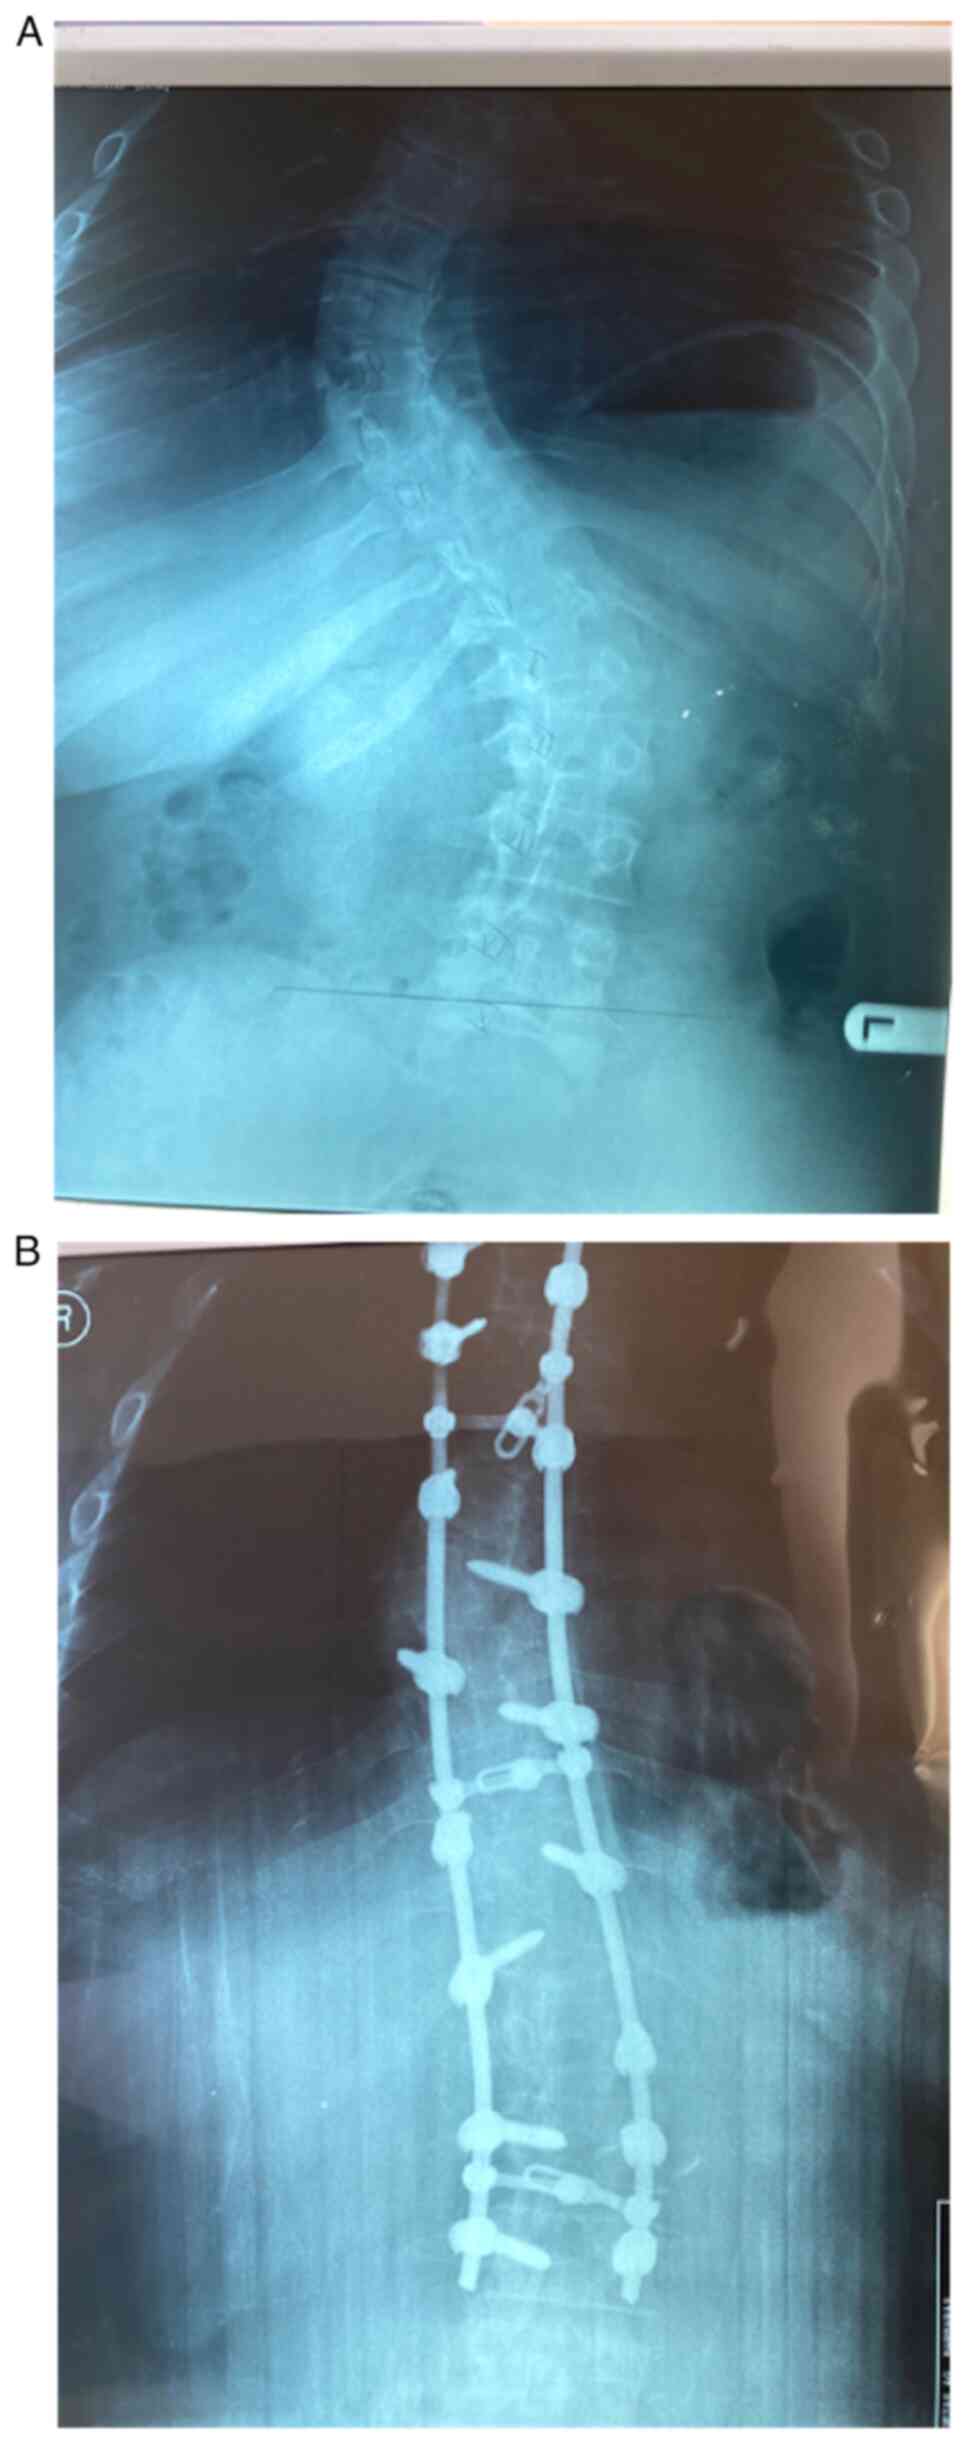

Acute‑on‑chronic slipped femoral epiphysis following posterior spinal fusion due to idiopathic scoliosis: Case report

The aim of this case report is to present a rare case of acute slipped femoral capital on a chronic slipped capital femoral epiphysis (SCFE) after spinal fusion due to idiopathic scoliosis. A 14 year old male patient underwent posterior spinal fusion due to idiopathic thoracic scoliosis. Post‑operatively, the patient presented with acute pain in the left hip and a reduced range of motion, which revealed acute SCFE. The patient was then referred to the Second Orthopaedic Department of Agia Sofia Children Hospital in Athens, and underwent percutaneous pinning of the left femur, after which he was discharged uneventfully. The follow up was excellent with no impact on the patient's daily life. The case described is extremely rare in the current literature. The significance of the pre‑operative planning is underlined by this case, as well as the need for the spinal surgeon to be aware of the possibility of acute pain in the hip in young adolescents, as SCFE is more common amongst this demographic.

Figure 1

Figure 2